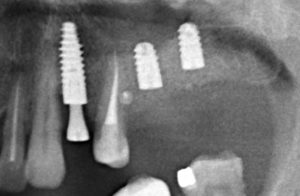

XiVE Dentsply Implants и немедленная имплантация: созданы друг для друга.

Недавно в журнале Dentsply Implants Magazine (#3 2015) вышла моя статья, посвященная имплантационной системе XiVE и немедленной имплантации. Для того, чтобы подогнать статью под формат журнала, мне пришлось ее слегка урезать. А сегодня я хотел бы представить ее вам в том виде, в каком задумал.